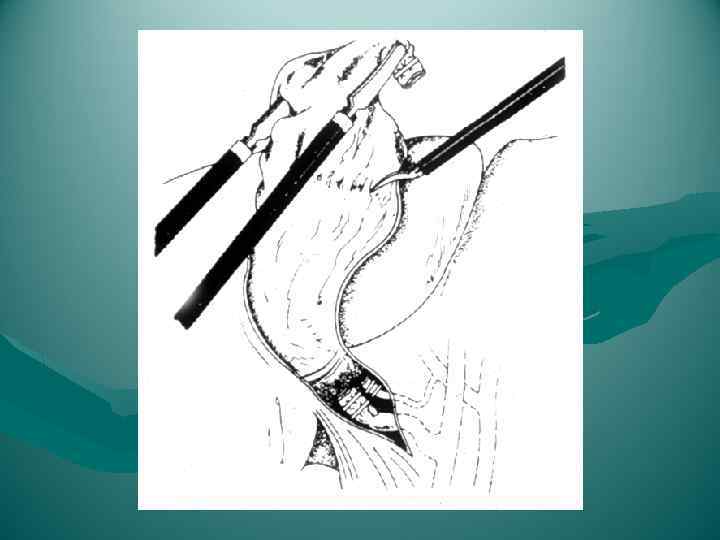

Резекция доли печени

Резекция доли печени